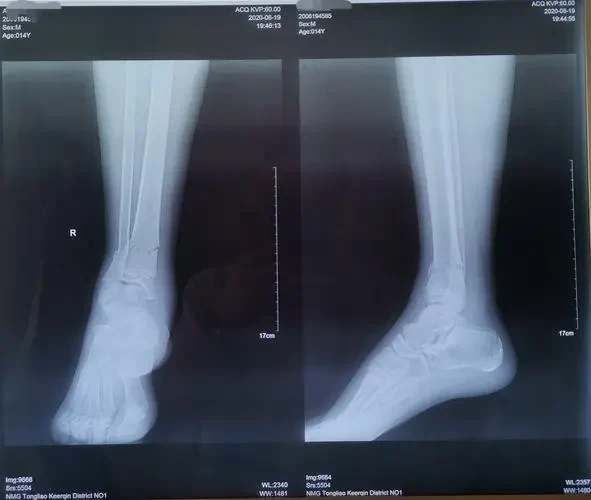

其次,影像学检查是确诊骨折的金标准。常见的影像学检查包括X线、CT和MRI等。X线是最常用的初步检查手段,其优点在于检出率高且费用低。而对于需要更加精细评估的骨折如颅骨和脊柱骨折,CT和MRI则更为适用。

根据影像学检查结果,医生可以清晰地看到骨折的部位、类型和严重程度,然后再制定个体化的治疗方案。